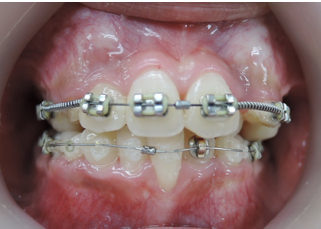

よく診る、難しい症例(奥歯の隙間)